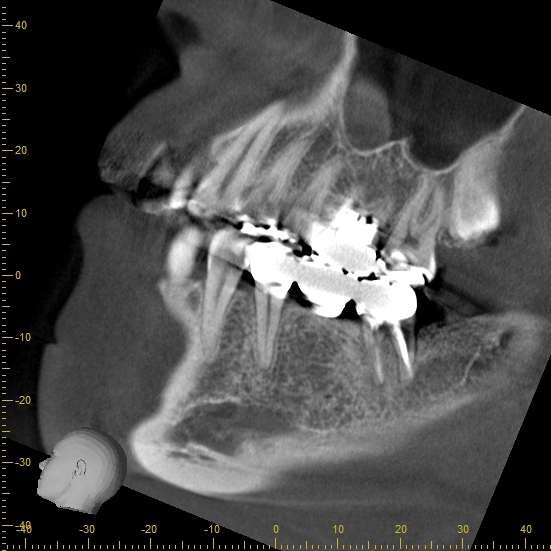

桶川にある歯医者、アズ歯科桶川院の歯科医師、鈴木篤士です。 1年ほど前に、神経の治療を受けた歯の違和感が続いていると他県から相談で来院された患者様です。 表面上は問題なく見えたため、レントゲンで確認させていただきました。 CTの画像です。 顔を横から見た図 顔を正面から見た図 緑の矢印の部分が周囲に比べて少し黒く見えると思います。 この部分は菌の影響で根の周囲にある骨が溶けている状態です。 まだ、あまり範囲は広がっていませんがこのままの状態で放置しておくと、菌がどんどん広がり、最悪の場合、抜歯になってしまう可能性があります。 これを治すには再度根の治療(根管治療)が必要です。 しかし、1度根管治療を受けた歯のやり直しは初めて神経を取る治療に比べ、難易度が上が理、成功率が下がります。 以前の治療の際にどういった内容の処置を受けていたのかにもよりますが、すでに歯の内部にたくさんの菌が存在している可能性、一度削っているため歯の強度が落ちている可能性、また、歯科医師によって手技が異なるため他院での治療方法がわからず手探りで始めることになる可能性があるからです。 イメージとしては下のような状況です 治療の流れ ①被せ物を外し、虫歯があれば除去する ②中にある土台などの材料を除去する ③根の内部に充填されている薬剤を除去する こうすることによって根の先の菌が溜まり炎症が起こっている部分に直接アプローチできるようになります。 この際とても重要になってくるのがラバーダムと呼ばれる、ゴムの器具です。 下の写真のように、歯の周囲に専用の器具と一緒に用い、治療の歯のみを周囲から分け、根管治療の際に唾液が中に入らないようにするために使います。 唾液中には数百億個もの菌が存在すると言われており、それが歯の内部に入ってしまっては薬などの効果も半減し治る確率が減ってしまいます。 しかし、日本の歯科医院で保険診療において使用している所はほとんどないのが現状です。 また、治療の精度を上げるために必要になるのがマイクロスコープです。 歯の内部は暗く細いため、肉眼やルーペで見ても正確に確認することはできません。 当院では、保険診療内外問わず、ラバーダム、マイクロスコープ、CT、ニッケルチタンファイルなど治療に必要なものは必ず使用するようにしています。 それでも治らないことがある程、根管治療は難易度の高い治療だと考えます。 今回の症例でも全ての器具を使用し治療を行いました。 治療後のCT画像です。 緑の矢印の部分が白くなっているのが分かると思います。 溶けていた骨が再生しています。 治療前後で比較します。 治療前 治療後 元々あった違和感も消え、大変喜んでいただけました。 根管治療はとても難しい治療です。 治療後の再発などで悩んでいる患者様も多く、セカンドオピニオンなど他県から来院していただくケースも増えています。 必ず治るとは言えませんが、できる限りの機材を使用し精度の高い治療を心がけております。 アズ歯科桶川院までお気軽にご相談ください。 治療期間 3ヶ月 治療費 保険診療 治療のリスク 歯が割れてしまう可能性がある